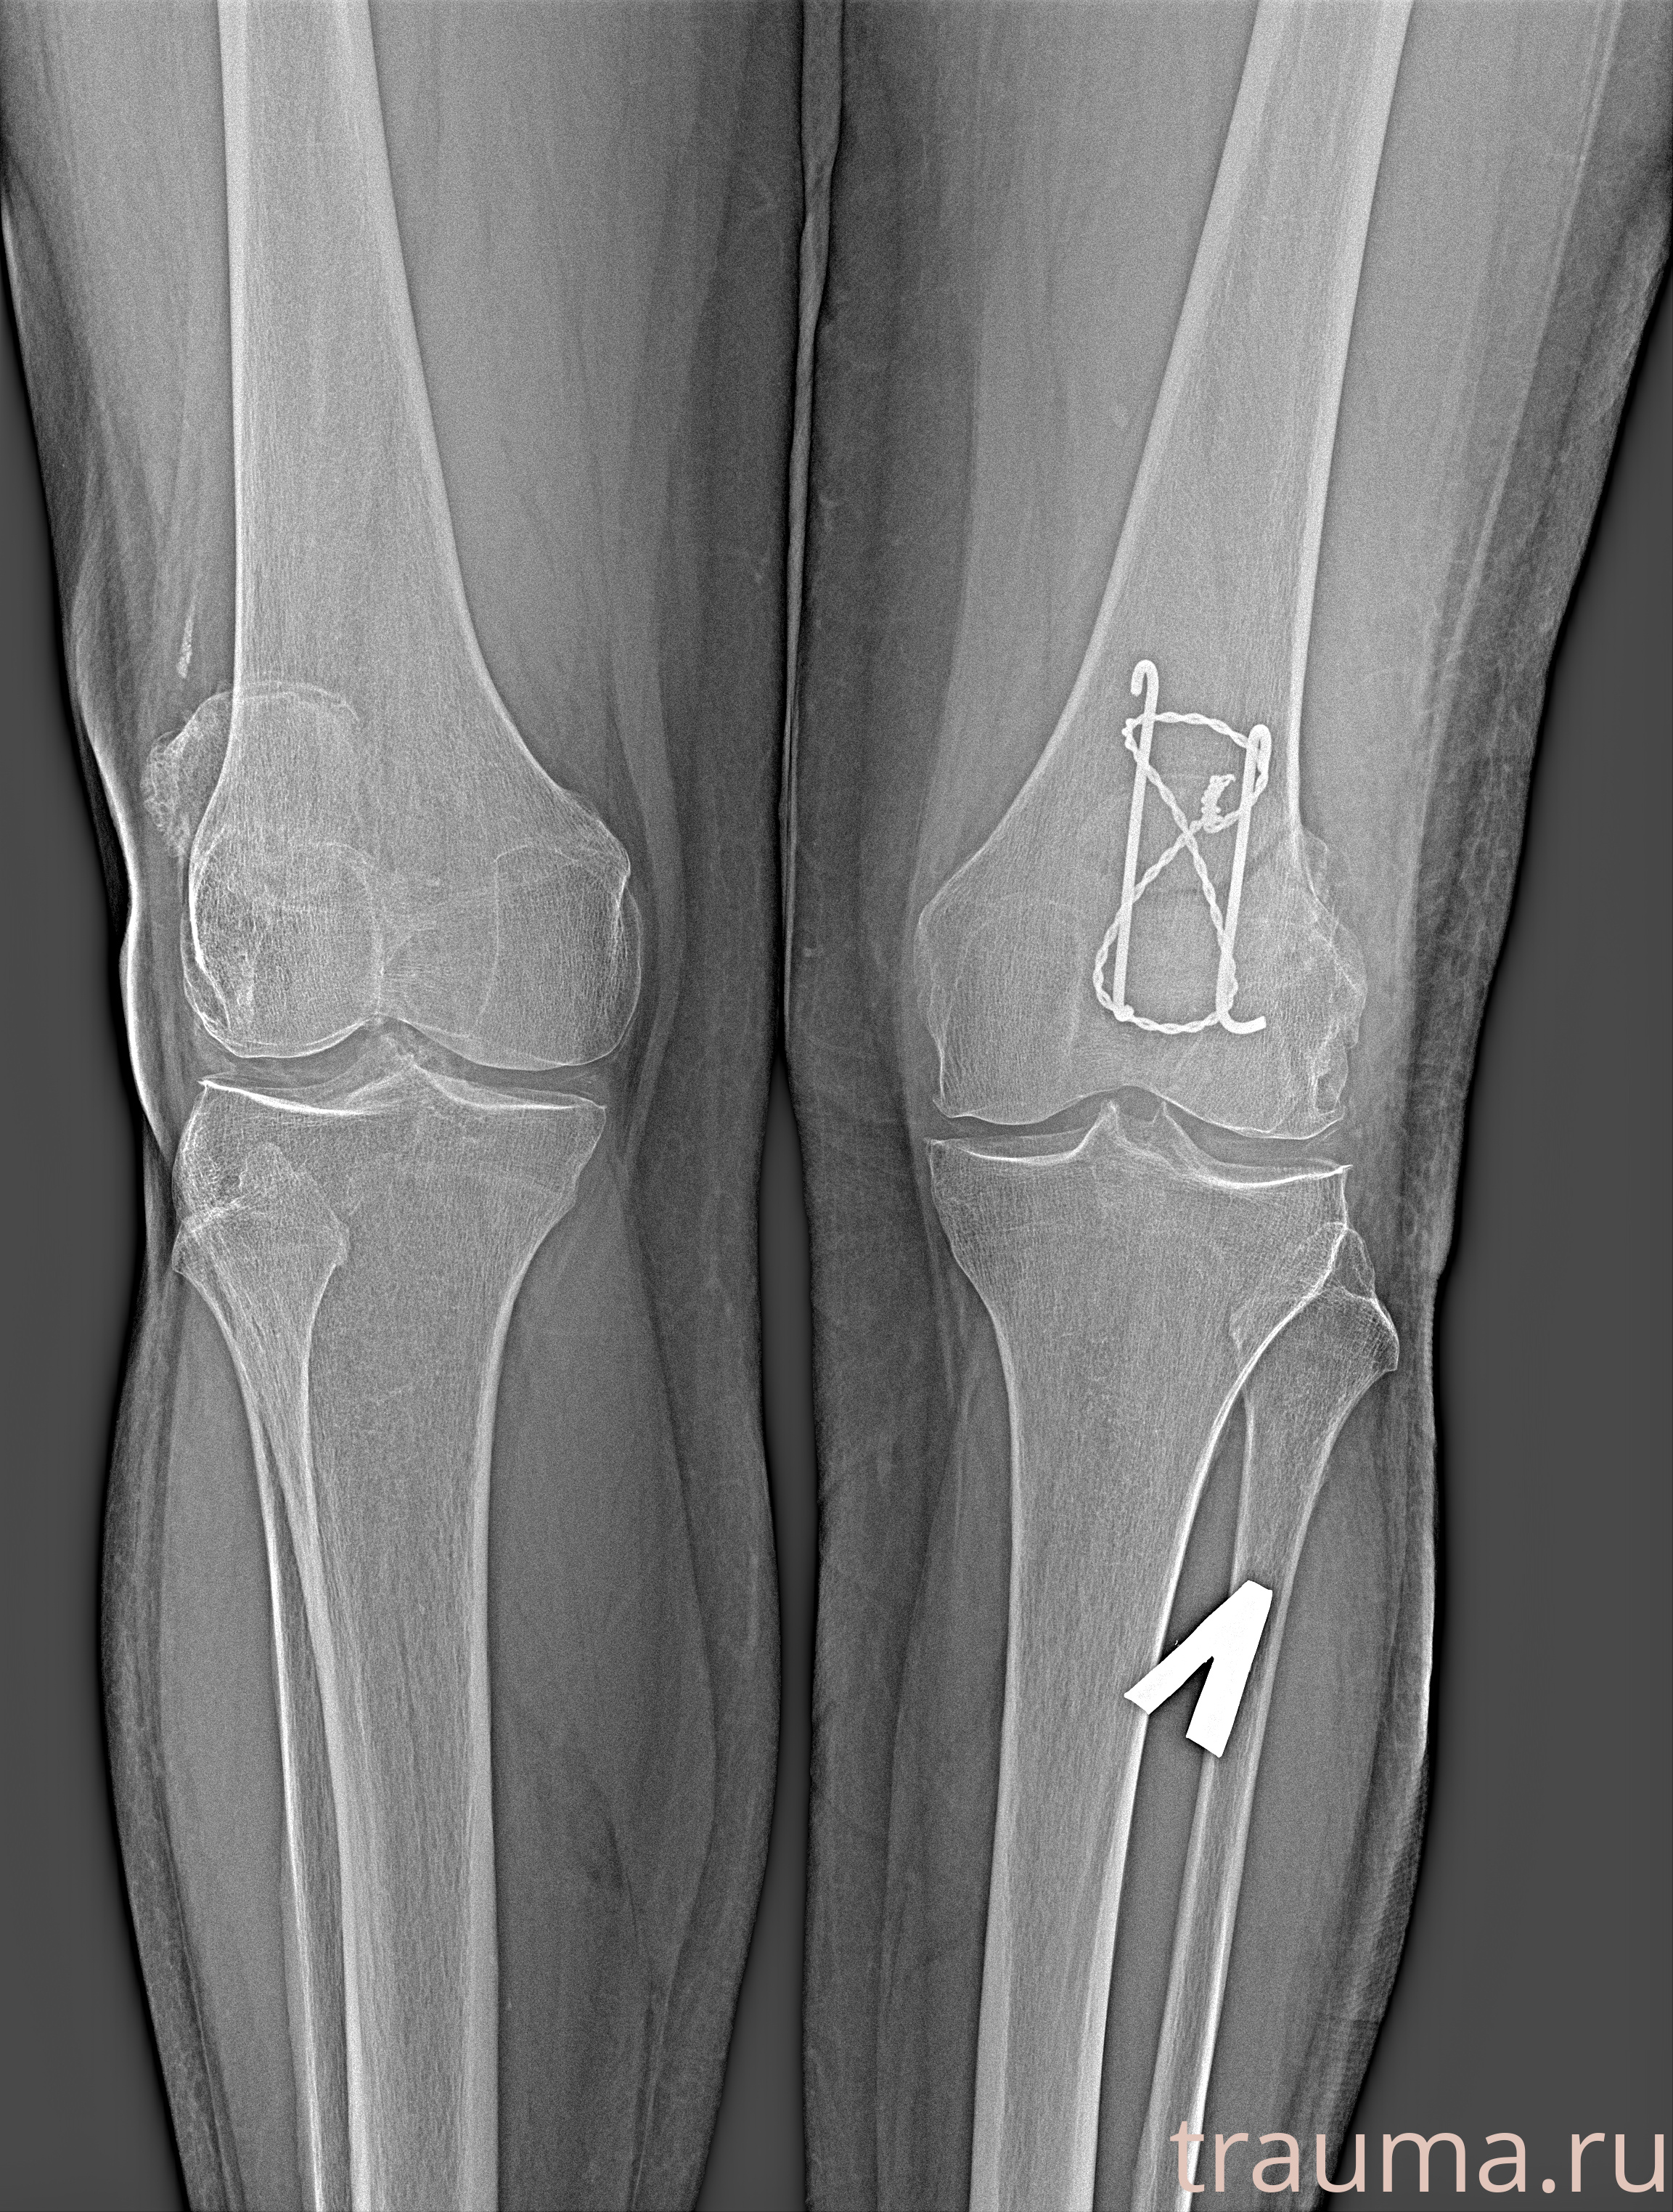

Рентгенограммы

Яркость: 1   Контраст: 1   Инвертировать: 0 Увеличение: 1

Перетаскивайте мышь вверх/вниз для контраста, влево/право для яркости. Прокрутка колесом изменяет масштаб. Нажмите Сбросить для возврата к исходному изображению. При увеличении держите мышь в той области, которую хотите рассмотреть.